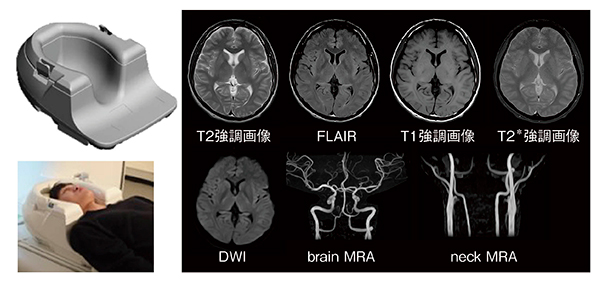

図1 Open Headコイル

コイル外観とセッティングの一例。Open Headコイルで撮像したボランティア画像では,頭部MRA,頸部MRAも撮像できている。